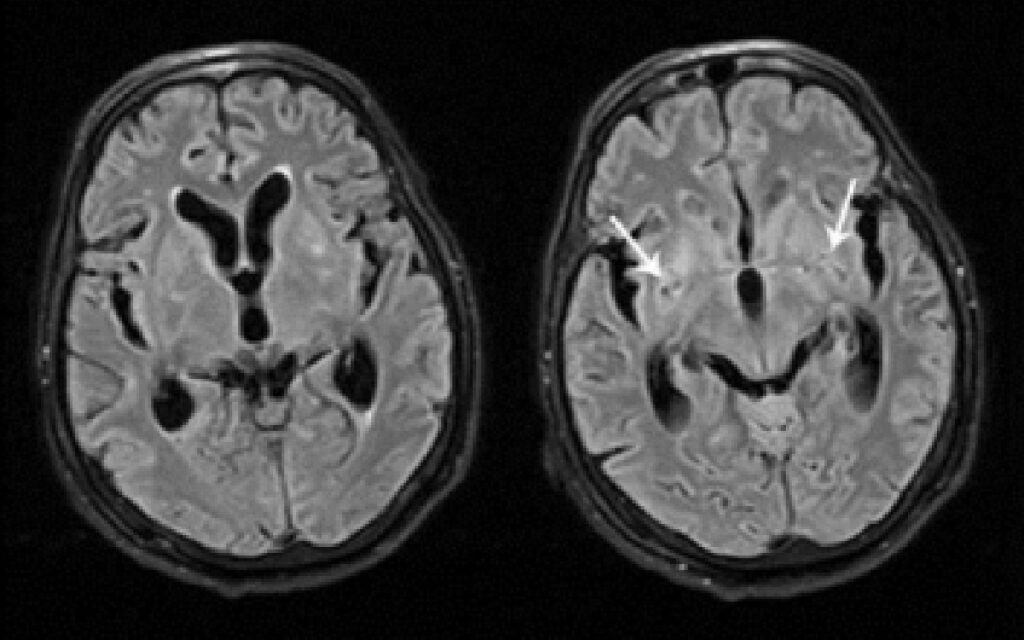

Según los apuntes médicos, la meningitis consiste en la inflamación de las membranas (meninges) que rodean al cerebro y la médula espinal.

Habitualmente, aunque no siempre, tienen una causa infecciosa como bacterias, parásitos, hongos, virus, ciertos medicamentos o tumores.